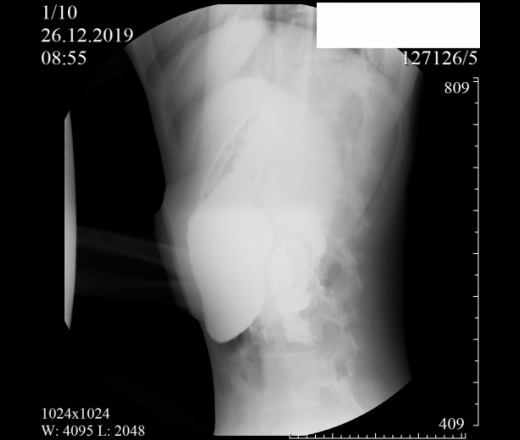

Девочка, 2004 г. Направлена с диагнозом ФНГ печени в онкоцентр. Приложены снимки рентгеноскопии ЖКТ. Помогите с интерпретацией, очень редко с этим работаем. Спасибо.

Как понимать аббревиатуру ФНГ? Не брался бы выность заключение после проведения Rg-скопии желудка, только по представленным снимкам. Можно однозначно сказать, что есть гипотония желудка( некотрые врачи используют термин гастроптоз).

"(красиво начали, жаль, оборвали) - гипотонус желудка, гипотонус луковицы ДПК, вероятный дуодено-гастральный рефлюкс, аорто-мезентериальная компрессия ДПК (стадия 1 или 2, не скажу - недостаточно снимков, скопию закончили рано), птоз тощей кишки и колоноптоз. "©

Ну, на Земле, еще в 1915 году (еще во времена Первой мировой войны) рентгенологом Hurst написано, что опущение желудка (гастроптоз) устанавливается на основании исследования с бариевой взвесью не стоя (errect position), а лежа (horizontal position)

писать "колоноптоз", имея такое положение толстой кишки, странно, а с "аорто-мезентериальной компрессией ДПК " согласен